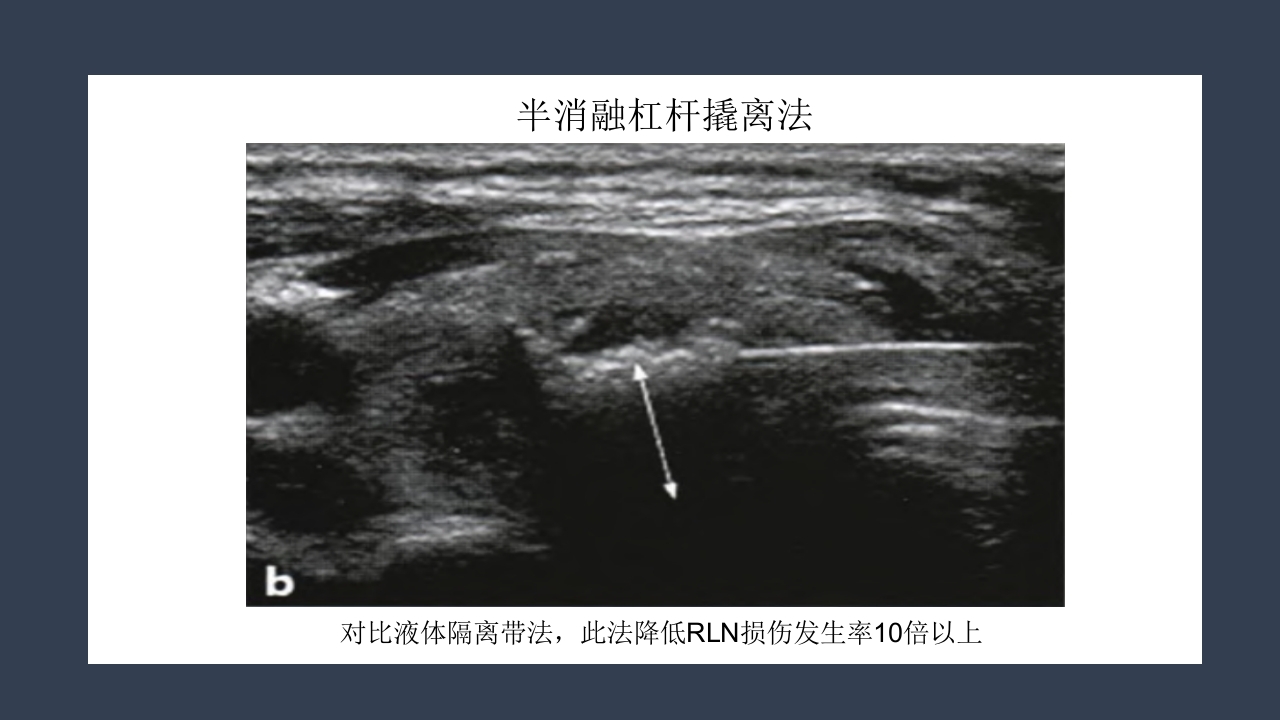

超声引导下甲状 腺结节射频消融 汇报人:xxx 时间:20XX年XX月 研究背景 甲状腺结节的患病率 尸体解剖:50.5% 人群普查可触及:3%-6% 超声发现非触及:20%-60% 男女比可达到1:4 甲状腺良性结节也有恶变可能 研究背景 Benign 甲状腺 结节 Malignant 5%-15% 2%恶性由 良性转变而 来 甲状腺结节的治疗方法 治 疗 传统手术切除 腔镜下切除 微创消融 甲状腺叶 全切除 次全切除 胸骨切迹 锁骨下 胸骨前乳晕 腋窝等 无水 乙醇 硬化 放射性 碘131植入 射频消融 微波消融 激光消融 传统手术切除 6-8CM的手术瘢痕 腔镜下切除 手术时间长,剥离面大,术后 疼痛强,是创伤较大的手术。 射频消融术 RFA治疗甲状腺结节的优势 ①微创或无创治疗技术是医学发展的大趋势。 ②...